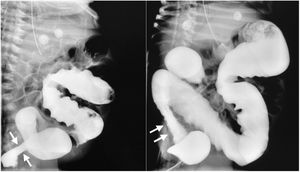

A plain abdominal x-ray was ordered, revealing important intestinal segment dilation (Fig. 1A). An orogastric tube was placed, with abundant output of bile, and a transrectal tube improved the abdominal distension (Fig. 1B). The infant had clinical signs of low cardiac output that responded to dobutamine infusion and presented with oliguria and elevated serum creatinine and blood urea nitrogen. Thyroid panel results were TSH 404 mIU/mL, total T4 0.420ng/dl, T4 0.058ng/dl, total T3 0.195ng/dl, T3 0.321pg/mL, for which treatment with levothyroxine was indicated. Feeding was started with extensively hydrolyzed formula in continuous infusion one week after her admission. Given the clinical presentation consistent with Hirschsprung’s disease, a contrast-enhanced barium enema was ordered that revealed an apparent transition zone in the rectosigmoid colon (Fig. 2), and so rectal irrigations were started. A rectal biopsy was taken, and high-resolution anorectal manometry was performed, documenting the rectoanal inhibitory reflex. Pericardial effusion, anemia, elevated direct bilirubin, and elevated transaminases were detected in the complementary evaluations.

The coexistence of hypothyroidism and Hirschsprung’s disease has been reported. Given that the thyroid hormones are essential for histogenesis, cell migration, and the cytoarchitecture of the central nervous system, the lack of those hormones has been suggested to favor the development of Hirschsprung’s disease, due to effects on gene expressions, ligands, receptors, apoptotic factors, or extracellular matrix proteins that affect cell migration or differentiation5. Thus, we had to rule out Hirschsprung’s disease in our patient, which we did, through rectal biopsy and anorectal manometry.